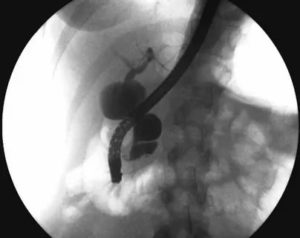

- интраоперационная или чрескожная холангиография;

- эндоскопическое исследование;

- КТ, которая опережает УЗИ по информативности и дает возможность исключить злокачественные процессы;

- Чрезкожная, интраоперационная и ретроградная эндоскопическая холангиография – помогают получить информацию о структуре желчных путей, в том числе перед хирургическим вмешательством. Минусами данного исследования являются инвазивность, противопоказания и осложнения, а также необходимость в проведении общей анестезии (при обследовании у ребенка);

- Магнитно-резонансная холангиопанкреатикография – наиболее эффективна в выявлении новообразований холедоха, проста в проведении, неинвазивна, в чувствительности несколько уступает ЭРХПГ.

- УЗИ (трансабдоминальная ультрасонография), которая эффективна, однако не всегда позволяет с точностью определить размер кисты;